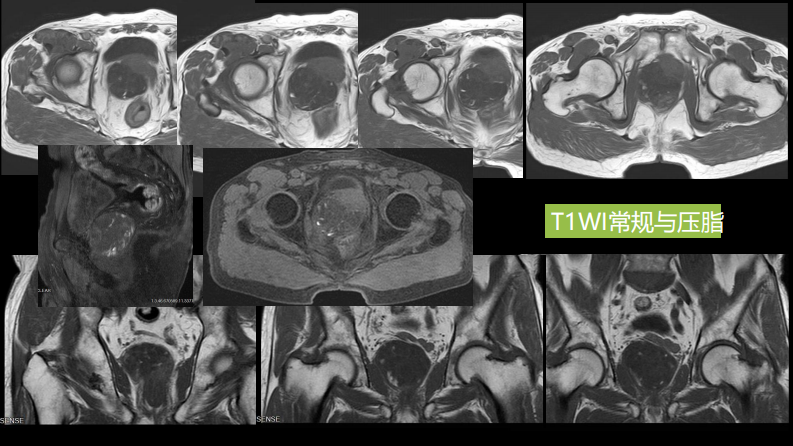

异位前列腺误诊为肿瘤.pdf